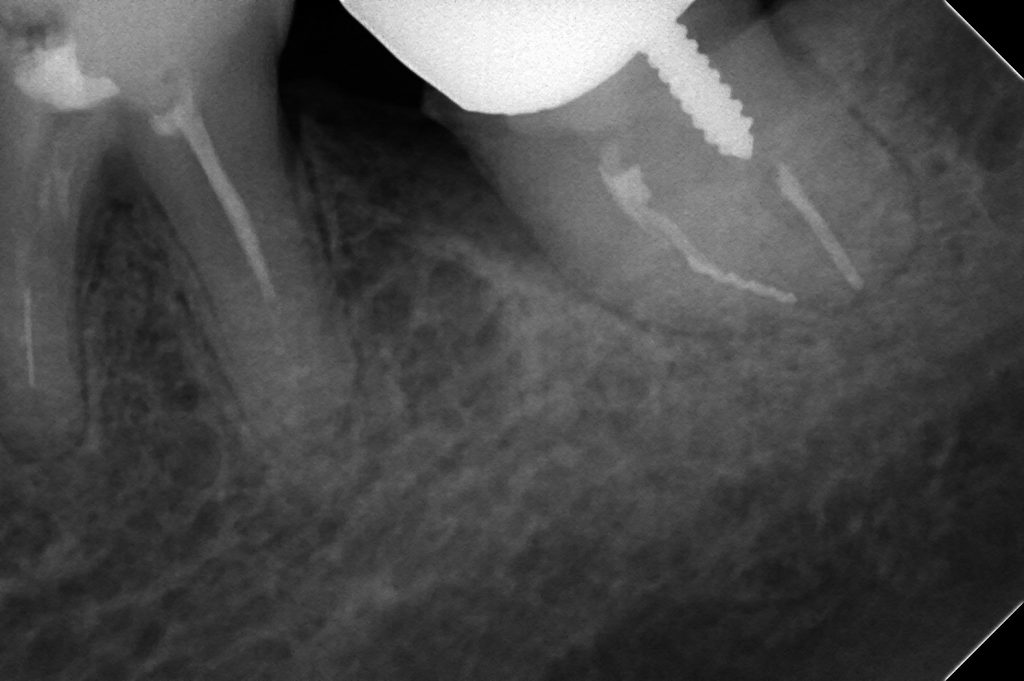

たとえば、下顎左側第二大臼歯の近心根に破折ファイルが認められます。

自発痛が強く、他院では抜歯してインプラントを勧められました。

当院で破折ファイルを除去したところ、とても喜んでくださいましたが、

「次回は土台を立てるので、自由診療か保険診療か選んでくださいね」

と患者さんに伝えたところ、

「先生、保険でお願いします」

という答えがかえってきました。

私は信じられず、とても驚いたことを記憶しています。